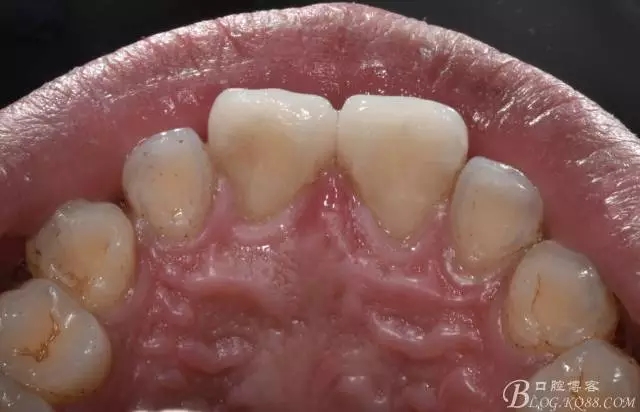

舌側照

640.webp (12).jpg